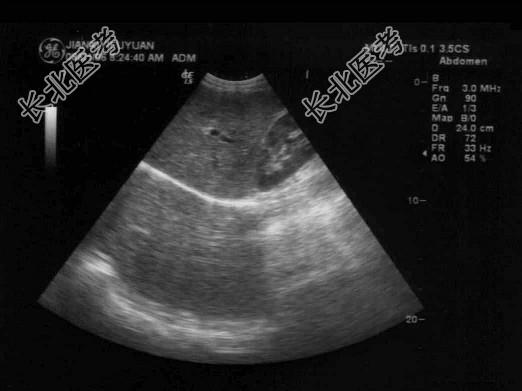

- 单项选择题右肝肋缘下向上扫查时常可见到镜面伪像,以下哪项是不正确的 ( )

A、正常肝脏:膈下为肝脏实像,膈上为肝脏虚像

B、肝内囊肿:膈下、膈上各有一个对称性肿瘤,前者为实像,后者是伪像

C、肝内肿瘤:膈下、膈上各有一个对称的肿瘤,前者为实像,后者是伪像

D、右侧胸腔积液时,以上镜面伪像消失

E、右侧胸腔积液时,以上镜面伪像更明显